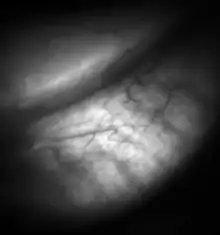

Meibomian gland dysfunction (also known as MGD) is a chronic disease of the meibomian glands, which is commonly characterized by obstruction of the end of the duct that delivers the secretion produced by the glands (called meibum) to the eye surface, which prevents the glandular secretion to reach the ocular surface. The dysfunction could be that the amount of secretion produced may be abnormal (either too little or too much meibum produced). Dysfunction could also be related to the quality of the meibum produced. MGD may result in evaporative dry eye, blepharitis, chalazion, unsealed lid during sleep, and meibomian gland atrophy.[2]

MGD causes the glands to be obstructed by thick, cloudy-to-yellow, more opaque and viscous-like, oily and waxy secretions, a change from the glands' normal clear secretions.[3][4] Besides leading to dry eyes, the obstructions can be degraded by bacterial lipases, resulting in the formation of free fatty acids, which irritate the eyes and sometimes cause punctate keratopathy. MGD has been described as "the most underrecognized, underappreciated and undertreated disease in ophthalmic care [...] so common as to be taken as ‘normal’ in many clinical practices".[5]